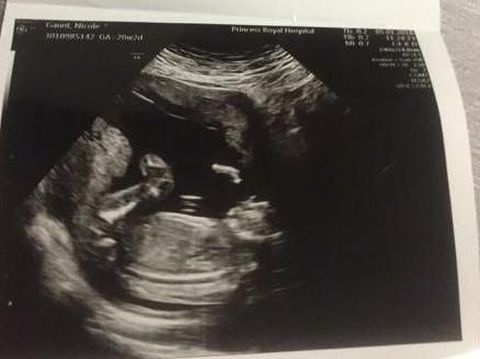

Nicole Gaunt dan pasangannya Jordan Garvie diberitahu bahwa bayi mereka memliki cacat lahir yang jarang terjadi. Pada masa di kandungan Nicole, dokter menyebutkan bayinya didiagnosis menderita anencephaly, penyakit yang mencegah tengkorak terbentuk dengan baik di dalam rahim.

"Mereka mengatakan kepala Jordan Junior tidak terbentuk dengan benar. Anencephaly pada dasarnya menghentikan bagian belakang tengkoraknya dari pembentukan sehingga dia akan lahir tanpa bagian utama dari otak, tengkorak dan kulit kepala," tambahnya.

Bayi di dalam kandungan Nicole GauntBayi di dalam kandungan Nicole Gaunt Foto: Facebook

Nicole tahu bahwa sebagian besar bayi dengan kondisi seperti itu tidak ada kesempatan untuk bertahan hidup dalam jangka panjang. Dokter juga tidak tahu berapa lama waktu yang ia miliki dengan bayinya. Wanita berusia 19 tahun ini pun sadar dirinya harus merencanakan pemakaman untuk bayinya yang belum lahir.